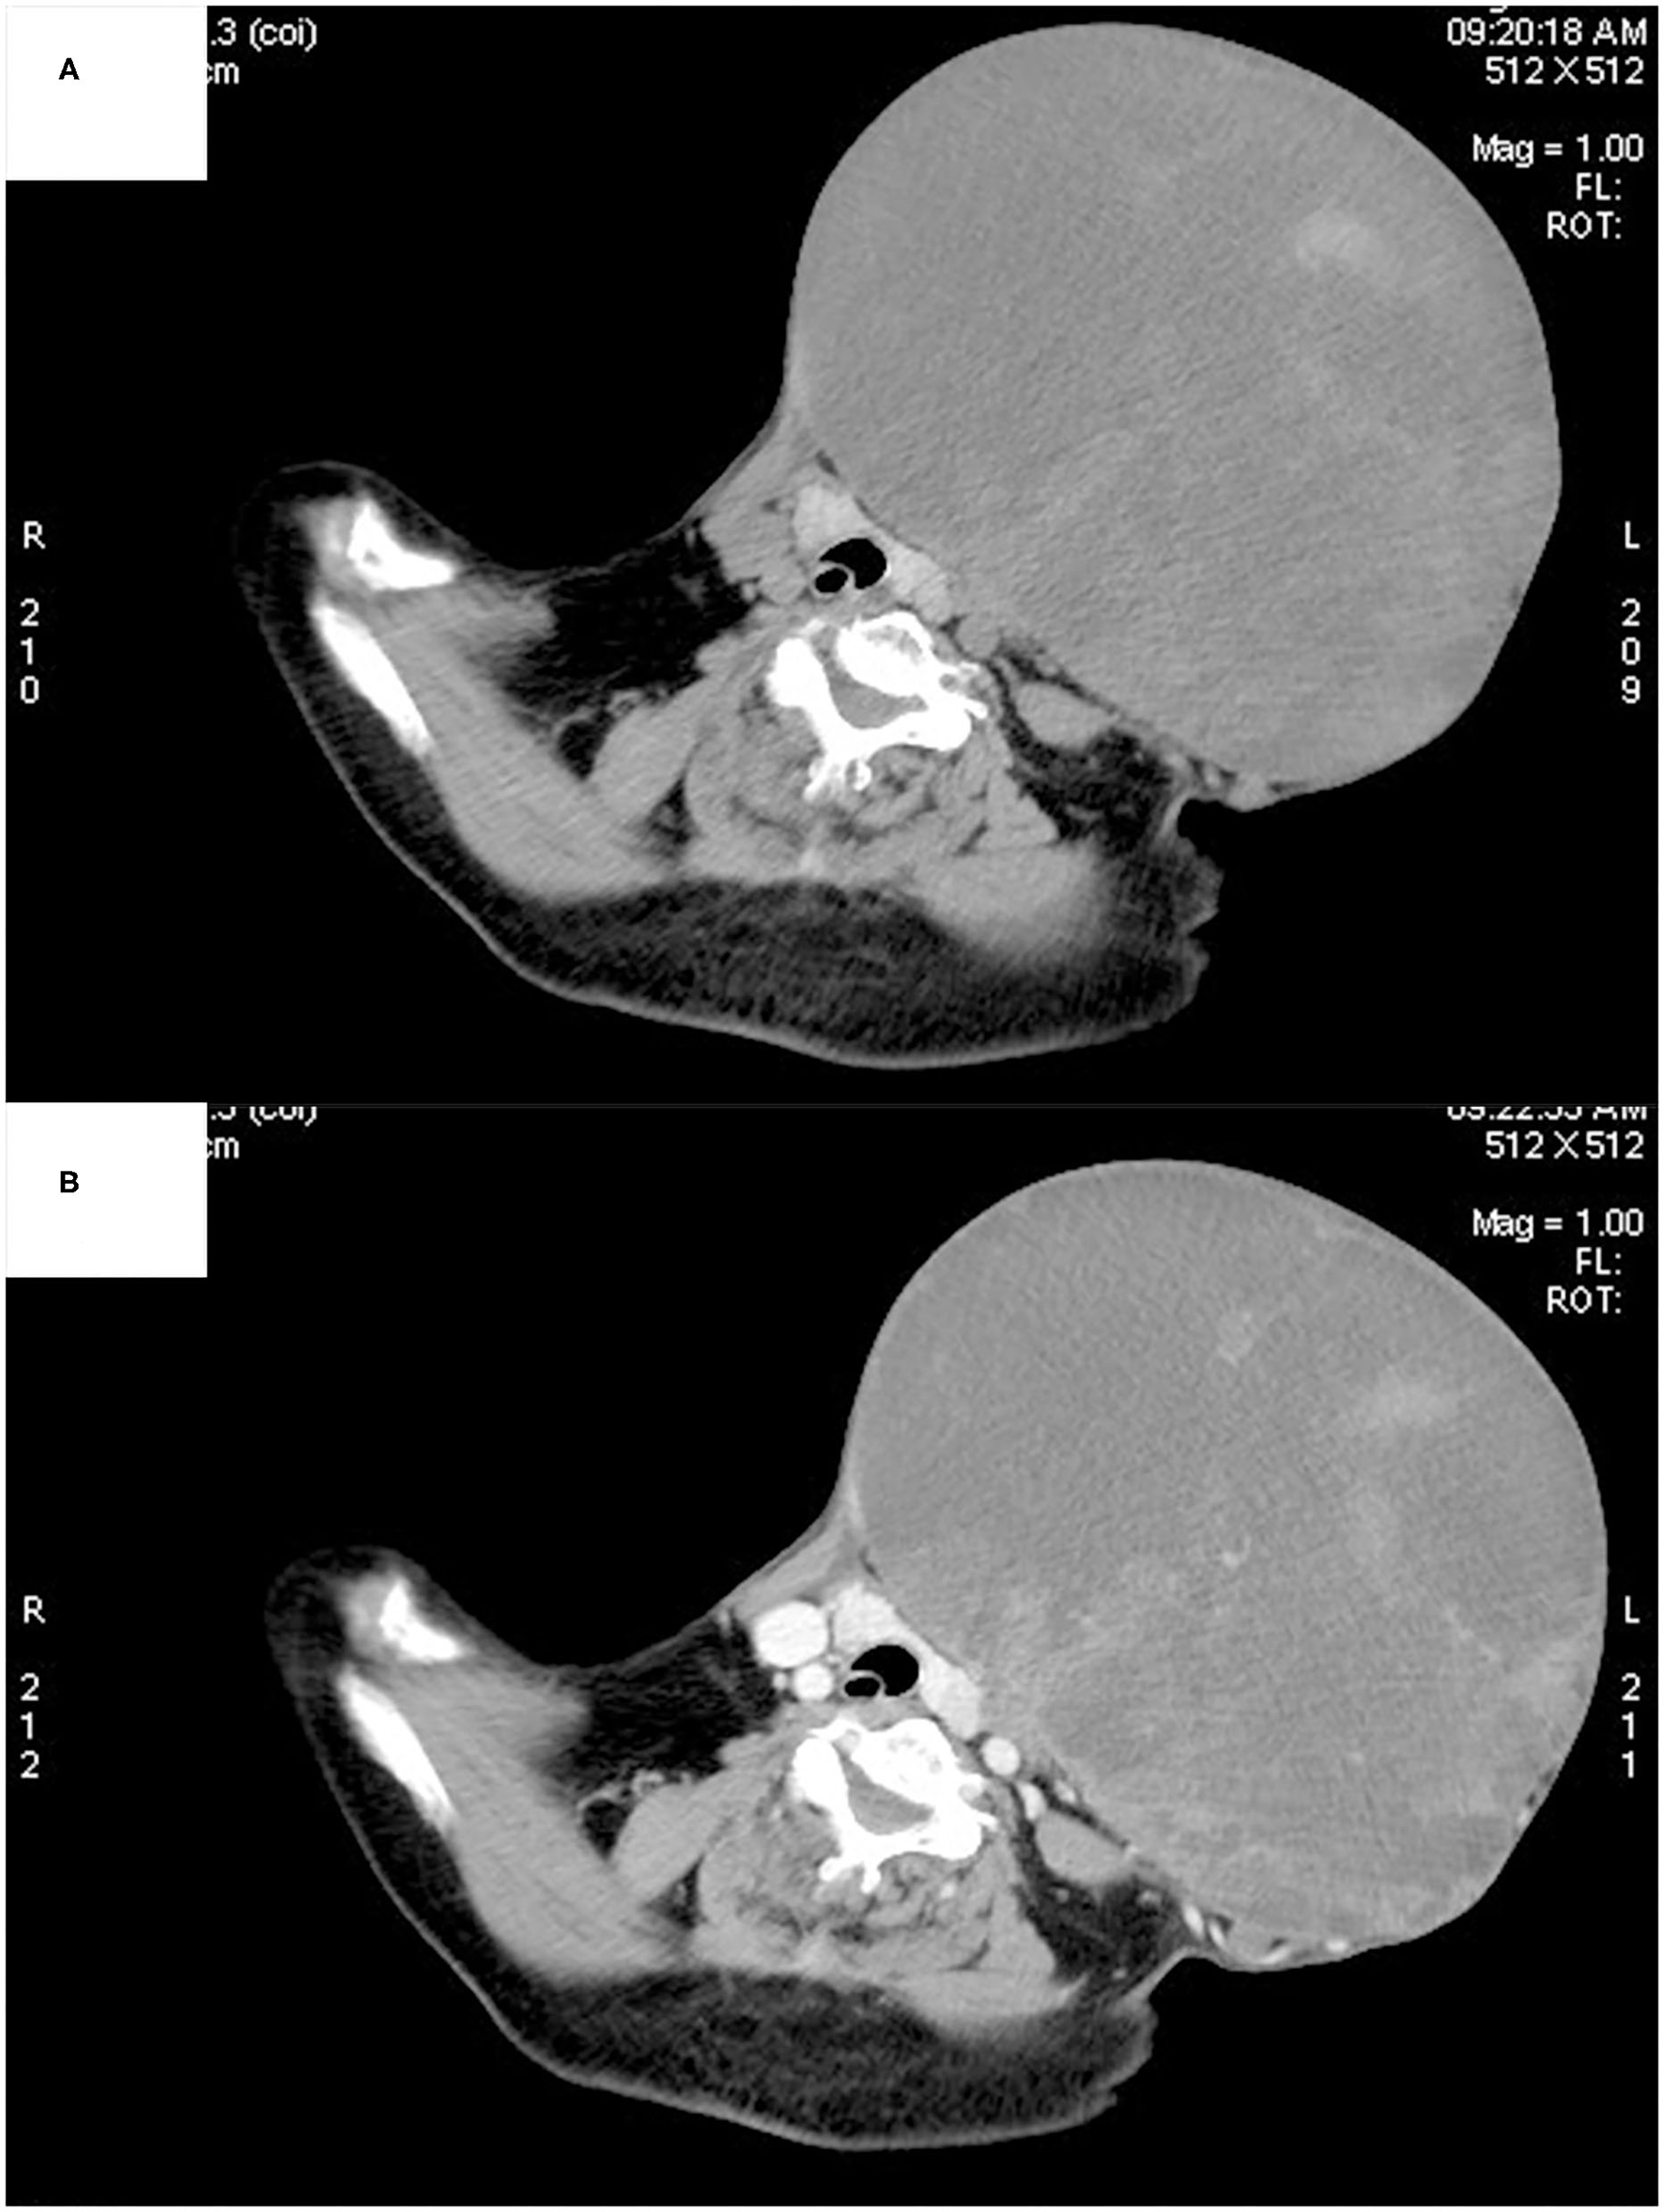

Ultrasonography showed a large mixed echogenic mass with a clear boundary and irregular shape in the middle of the neck. The trachea and thyroid gland were squeezed to the right side. The thyroid had normal morphology, and the capsule was normal. Several heterogeneous hypoechoic and mixed echoes were found in the left level I and level II regions of the neck. Computed tomography also showed a large mixed-density lesion in the left anterior neck, with a maximum cross-sectional area of ~22 × 16 cm. The internal density of the mass was uneven, with patchy high-density shadows. The CT value of the solid area was ~55 Hounsfield units (HU) and that of the cystic area was ~20 HU (Figure 2A). After contrast infusion, there was no obvious enhancement of the mass (Figure 2B). Several small nodular lesions with radiological features similar to those of the large mass were seen in the left parapharyngeal space. No obvious enlarged lymph nodes were found nearby. The trachea was found moderately deviated to the right side, but there was no tracheal collapse.

Figure 2

Computed tomography showed a large mixed-density lesion in the left anterior neck, with the trachea and thyroid gland being squeezed to the right side. The internal density of the mass was uneven, with patchy high-density shadows (A). No obvious enhancement was found in the arterial phase (B).